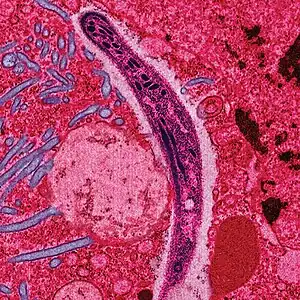

False-colored electron micrograph showing a malaria sporozoite migrating through the midgut epithelium of a rat